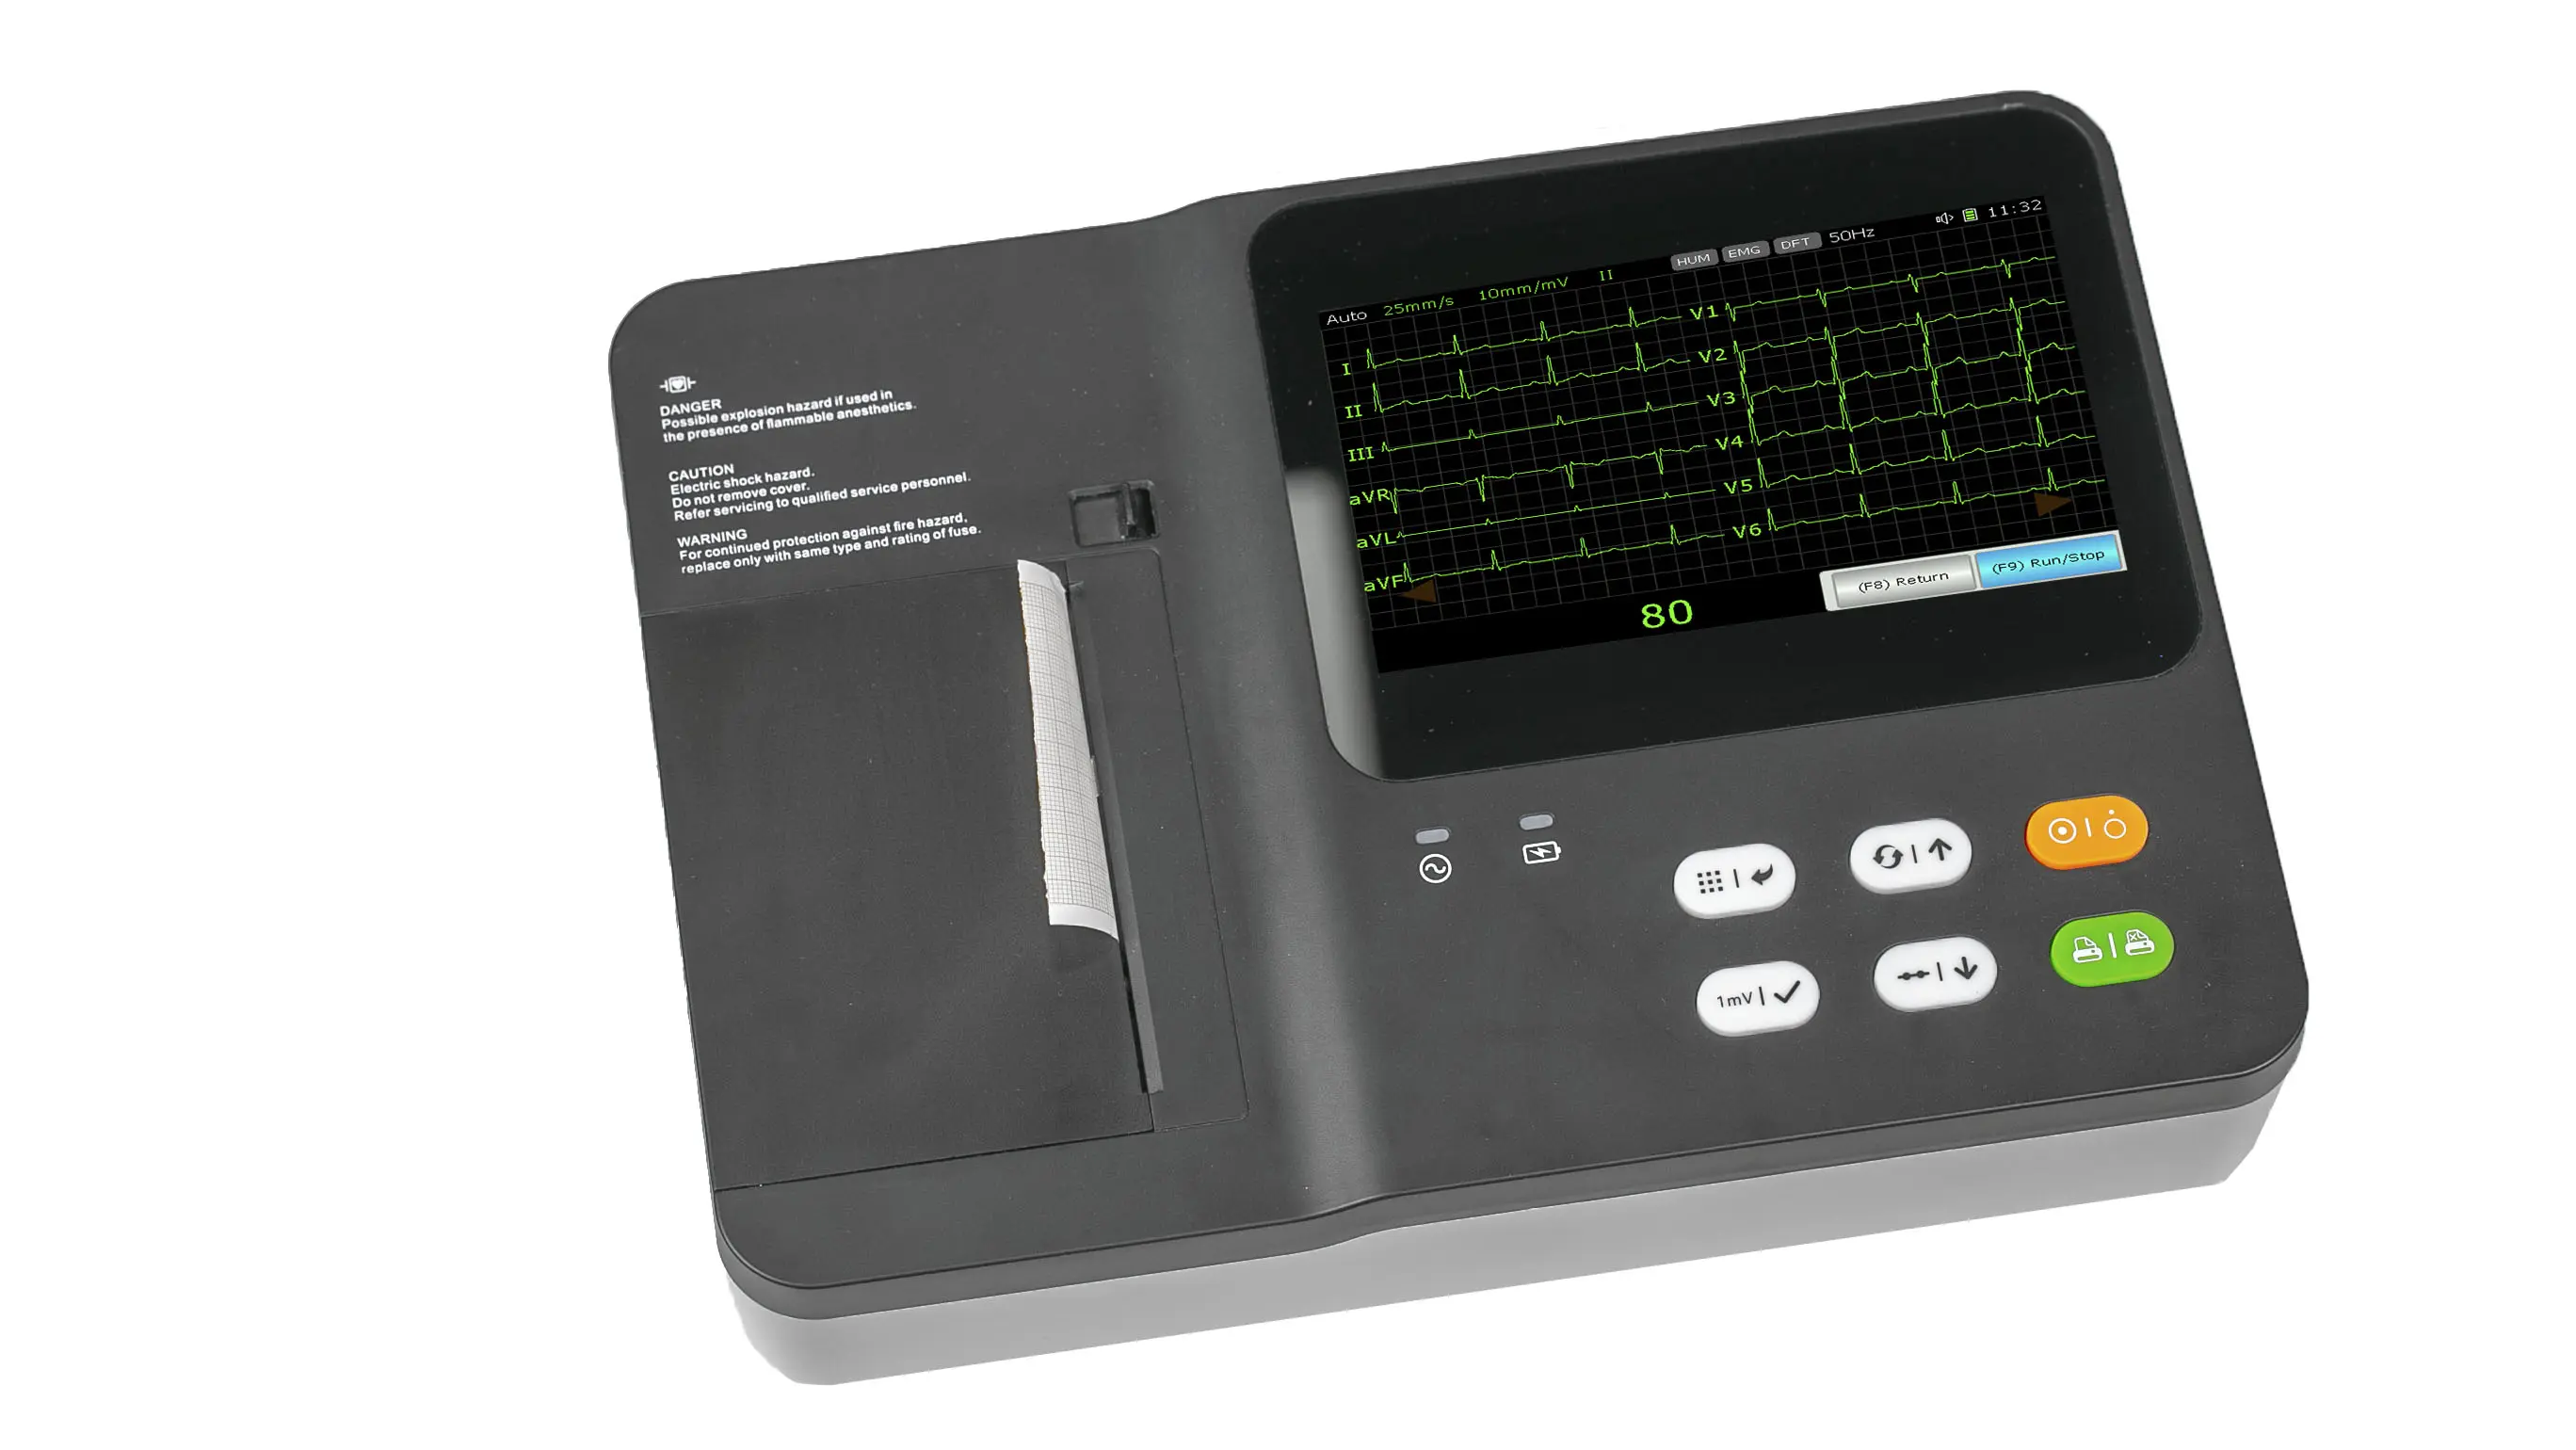

3 Channel 7 Inch Touch Screen Portable Electrocardiograph ECG Machine

3 Channel 7 Inch Touch Screen Portable Electrocardiograph ECG Machine